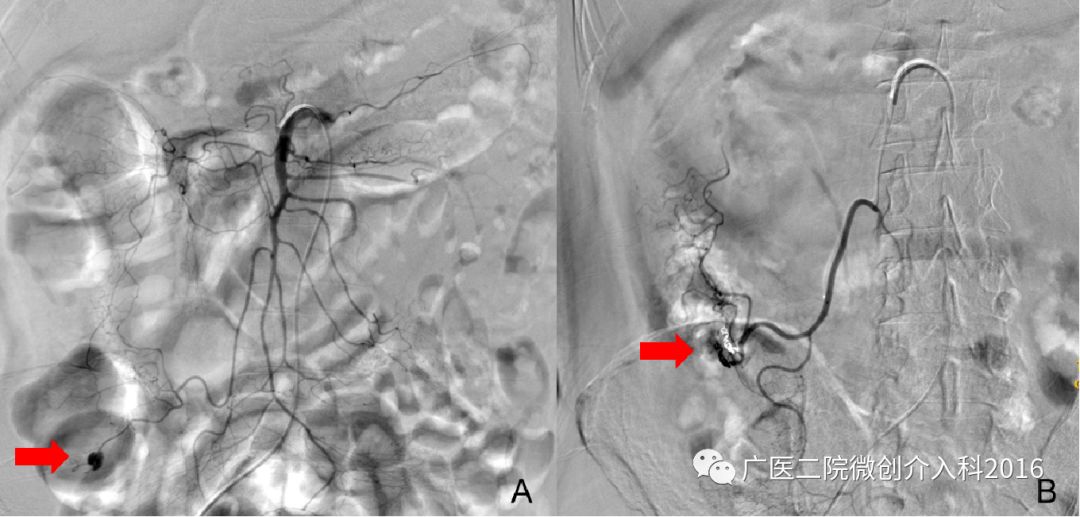

患者持续排血便3天,肠镜未能找到明确出血点。图A行肠系膜上动脉造影显示造影剂浓聚、外渗,明确诊断为回盲部肠道出血,出血血管为回结肠动脉。经微导管注入弹簧圈栓塞出血动脉,图B再次造影示原出血征象消失,患者出血停止。

患者拉鲜血便1天余,出血量大约1000ml。肠镜提示直肠出血并行止血夹钳夹止血术,但患者仍出血不止。图A行肠系膜下动脉造影显示直肠区域造影剂浓聚、外渗,明确诊断为直肠出血,出血血管为直肠上动脉。经微导管注入弹簧圈和明胶海绵颗粒栓塞出血动脉,图B再次造影示原出血征象消失,患者出血停止。